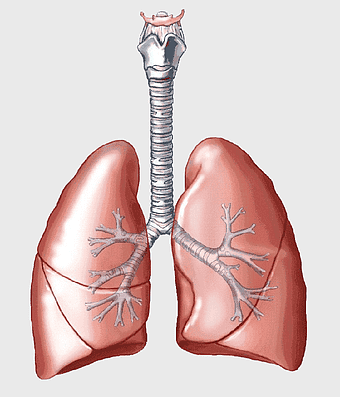

Pulmonary edema symptoms, chronic obstructive pulmonary disease diagram, kidney failure effects on lungs, pulmonary circulation illustration, lung disease diagnostic, respiratory health visuals, human anatomy respiratory system, PNG

- pulmonary edema symptoms

- chronic obstructive pulmonary disease diagram

- kidney failure effects on lungs

- pulmonary circulation illustration

- lung disease diagnostic

- respiratory health visuals

- human anatomy respiratory system